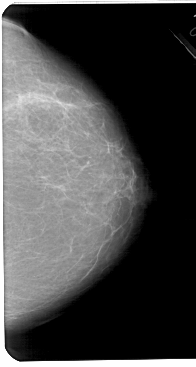

A_1441_1.LEFT_CC

LEFT_CC LINES 5491 PIXELS_PER_LINE 2986 BITS_PER_PIXEL 12 RESOLUTION 43.5 OVERLAY

FILE: A_1441_1.LEFT_CC.OVERLAY

TOTAL_ABNORMALITIES 1

ABNORMALITY 1

LESION_TYPE CALCIFICATION TYPE PLEOMORPHIC DISTRIBUTION CLUSTERED

ASSESSMENT 4

SUBTLETY 2

PATHOLOGY BENIGN

TOTAL_OUTLINES 1

BOUNDARY